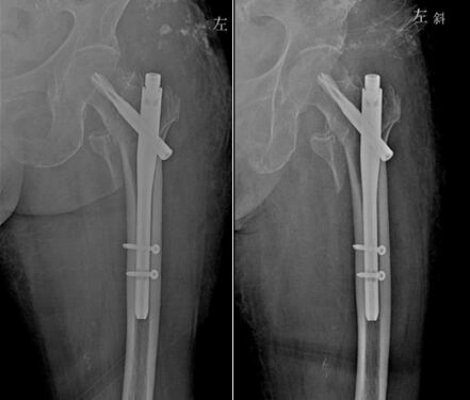

髓内钉内固定可以使应力更均匀地分布于内植物与骨之间,因其接近骨骼轴线,能更好地对抗弯曲应力[17]。髓内钉固定骨质疏松性骨折,可以使患者早期负重,同时还能更好地保护骨折周围软组织。髓内钉内固定最薄弱的区域是置入交锁钉的干骺端[18]。这个区域的髓腔较宽,主钉与皮质不接触,因此结构的稳定性依赖于螺钉-主钉界面[19]。当选用髓内钉治疗骨质疏松性骨折时,应重点关注此区域,因为骨质量差会影响交锁螺钉的稳定。

随着髓内钉的不断更新迭代,设计和手术技术的双重提高,髓内钉治疗骨质疏松性骨折的适应症也逐渐扩大。例如:多平面交锁固定有助于提高骨折的稳定性,降低畸形愈合的风险[20];交锁螺钉替换为螺旋刀片,能增加应力负荷承载面积,将应力分散至更多的骨组织上,从而减少作用于髓内钉结构的应力[21];具有角度固定的交锁螺钉,可以通过减少交锁螺钉的摆动,实现更坚强的内固定[22]。轴向应力负荷的作用下,螺旋刀片的刚度比交锁螺钉增加41%,强度增加20%[23]。虽然,生物力学研究证实了以上新设计髓内钉的有效性,但是这些研究均为轴向应力负荷下的稳定性,还需进一步研究其在扭转应力和人体正常生理负荷下的稳定性。